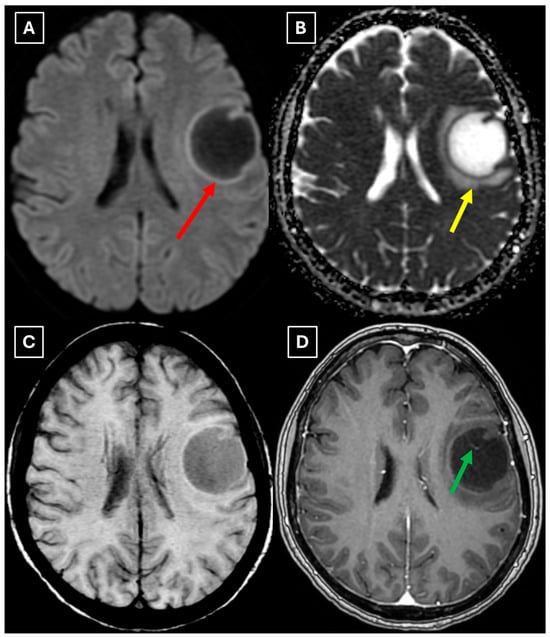

Figure 3. MRI scan of the brain. (A): Axial trace image of diffusion-weighted imaging (DWI) shows slight diffusion restriction in the lesion wall when correlated with (B): dark signal on apparent diffusion coefficient (ADC) maps in the wall of the lesion, with no central diffusion reduction observed. (C): In the corresponding axial slice of the susceptibility-weighted imaging (SWI) sequence, there is no evidence of blood products within the lesion. (D): On the axial postcontrast T1-weighted imaging, there is no contrast enhancement in the lesion, although a central vein-like structure is observed. Red arrow—diffusion restriction, yellow arrow—perifocal vasogenic edema, green arrow—central vein sign.

A repeat MRI before surgery showed that the lesion had reduced in size with no pathological contrast uptake persistence, with surrounding perifocal edema (Figure 4 and Figure 5). Given the improved results, the medical team suspected a demyelinating disease rather than a tumor and surgery was canceled. For diagnostic purposes, a lumbar puncture was performed. Cerebrospinal fluid (CSF) analysis excluded neuroinfection. Blood tests and CSF were examined according to the demyelinating disease protocol. Oligoclonal antibodies were negative in both the CSF and blood serum. Aquaporin-4 (AQP-4) antibodies were not found in the blood serum, and myelin oligodendrocyte glycoprotein (MOG) antibodies were also negative.

Figure 4. Two-week follow-up MRI scan of the brain. (A): Axial T2-weighted image shows a hyperintense and homogenous left frontal lobe lesion with well-defined borders. The lesion decreased from 37.34 mm × 34.85 mm (AP × LL) to 24.87 mm × 29.71 mm (AP × LL). A relatively extensive perifocal edema again persists, involving the white matter with relative spare of the white matter adjacent to gray matter; however, there is no mass effect or midline shift. (B): In the axial FLAIR the lesion appears with a more hypointense center and hyperintense peripheral rim at the lesion margins. Given the observed changes over a 2-week period and the decrease in the lesion’s size, an astrocytoma is considered less likely. Red arrow—indistinct formation, yellow arrow—perifocal vasogenic edema.

Figure 5. Two-week follow-up MRI axial scan of the brain. (A): Axial trace from diffusion-weighted imaging shows a higher signal along the peripheral parts of the lesion with the absence of cytotoxic edema when correlated with (B): the ADC map. (C): Central vein sign is positive on the susceptibility-weighted imaging sequence and (D): axial postcontrast T1-weighted sequence. These findings were not typical for low-grade astrocytomas. Red arrow—diffusion restriction, yellow arrow—perifocal vasogenic edema, green arrow—central vein sign.

Finally, we provide a high-resolution MRI follow-up of two months’ duration showing near-complete regression of the lesion after corticosteroid therapy. The lesion decreased from 37.34 mm × 34.85 mm (AP × LL) to 24.87 mm × 29.71 mm following two weeks of corticosteroid therapy and after almost two months from the first MRI scan to minimal patchy contrast enhancement (Figure 7D). This marked decrease in the size of the lesion gives strong evidence that a demyelinating rather than neoplastic process is present.

There are no pathognomonic features for tumefactive demyelinating lesions, but there are still some MRI findings that support the diagnosis. TDLs appear larger than 2 cm and are most often located in the frontal or parietal regions. The supratentorial white matter, especially in subcortical and periventricular locations, is commonly affected. On T1-weighted images they usually demonstrate hypointensity and hyperintensity on T2-weighted images, consistent with demyelination. These lesions have a varying degree of perifocal edema and mass effect, but both are usually mild relative to the lesion size in comparison to neoplasms or abscesses. The most characteristic enhancement pattern is the open-ring (incomplete rim) enhancement, which is significantly more common in TDLs than closed-ring enhancement. The open ring typically faces the cortex or gray matter and is considered a strong supportive feature for TDL diagnosis [3,11,18]. Contrast enhancement is not a universal feature, as Lucchinetti et al. (2008) [1] reported that approximately 5% of TDLs on postcontrast T1-weighted MRI did not show enhancement in their study. This finding was also observed in this case (Figure 3D), as well as in the case presented by Zafar et al. (2022) [19]. Therefore, the absence of enhancement does not necessarily exclude a demyelinating pathology.

Another MRI feature strongly associated with TDLs is a central vein sign (CVS), which was also observed in this case (Figure 3, Figure 5, and Figure 7), currently being considered for inclusion in MS diagnostic criteria. On SWI or T2-weighted sequences, CVS appears as a thin hypointense line or dot less than 2 mm in diameter, visible in at least two planes, and running partially or completely through the center of a lesion [2]. Although most studies of the CVS have focused on MS and radiologically isolated syndrome, the CVS is also applicable for TDLs, representing an atypical variant of MS. In radiologically isolated syndrome, Suthiphosuwan et al. (2019) [21] reported a median of 87% CVS-positive lesions per case, underscoring its strong association with inflammatory demyelination [2]. In the TDL cohort described by Ongphichetmetha et al. (2024) [2], CVS was observed in approximately half of the patients, while open-ring enhancement occurred at a similar frequency of around 50%, with both features supporting an inflammatory demyelinating rather than neoplastic process.

We also found similarities between this case and the classical imaging features of TDLs described in the literature. Hypoattenuation on noncontrast CT corresponding to enhancing areas on MRI is another useful imaging finding in TDLs [10], which may be explained by the tissue rarefaction caused by the active demyelination rather than increased cellularity, which is seen in tumors, thereby supporting the use of MRI with noncontrast CT in TDL diagnosis. Furthermore, restricted diffusion along the lesion margin with elevated central ADC values, in contrast to neoplasms which more commonly show central diffusion restriction, have been described as a commonly presenting feature of TDLs [3,4,10], which was also observed in this case (Figure 5A,B).

In this case, despite the presence of a T2/FLAIR mismatch sign (Figure 2), several imaging characteristics were more suggestive of a TDL rather than IDH-mutant astrocytoma. The lesion was located in juxtacortical white matter and had cortical sparing, which is unusual for IDH-mutant astrocytomas, since they typically have been shown to infiltrate and expand the cortex. The diffusion restriction at the lesion margin with centrally elevated ADC values was more consistent with reported DWI findings of TDLs and contrasted with the central restriction often seen in gliomas. The mass effect was mild in comparison to the overall lesion size, favoring demyelination rather than neoplasm in this case. Additionally, the lesion had a central vein sign, as described above, a radiological sign supportive of inflammatory demyelination. The combination of cortical sparing, peripheral diffusion restriction, mild mass effect, and the appearance of central vein sign represented strong features that raised suspicion of a tumefactive demyelination lesion.